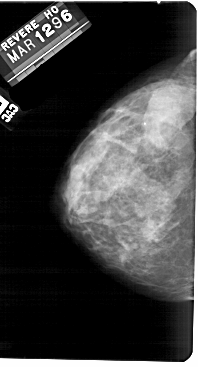

A_1256_1.LEFT_MLO

LEFT_MLO LINES 5491 PIXELS_PER_LINE 2851 BITS_PER_PIXEL 12 RESOLUTION 43.5 NON_OVERLAY